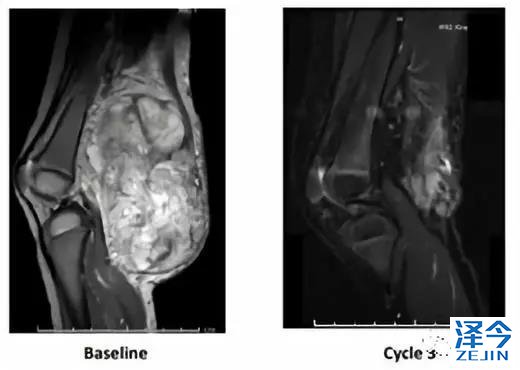

第一位是小患者珍妮,她在2岁的时候腿上长了一个巨大的婴儿型纤维肉瘤,化疗无效,当时唯一的选择就是截肢。这对珍妮来说将会影响她的一生。

万幸,她的肿瘤被检测出有NTRK3-ETV6突变,顺利参与到了我的临床试验中。

3个周期的治疗后,她的肿瘤几乎完全消失。再经过手术取出剩下的肿瘤,她的腿保住了!